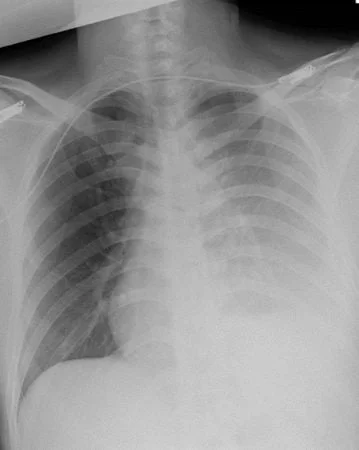

Ảnh chụp X-Quang của bệnh nhân C.

TS.BS Trương Nguyễn Hoài Linh, Khoa Phẫu thuật Tim mạch – Lồng ngực cho biết, bệnh nhân C. nhập viện cấp cứu trong tình trạng mất máu nhiều, choáng, mạch nhanh, huyết áp tụt, khó thở, da niêm xanh. Ngực trái có vết thương do bị đâm bởi vật sắc, nhọn.

“Kết quả chẩn đoán cho thấy có tràn máu màng khối lượng rất lớn, nghi ngờ có vết thương tim nên bệnh viện kích hoạt quy trình báo động đỏ, vừa hồi sức, vừa nhanh chóng chuyển bệnh nhân đến phòng mổ, bỏ qua thủ tục nhập viện thông thường để cứu sống bệnh nhân”, BS Linh cho hay.

Theo BS Linh, phẫu thuật mở ngực bệnh nhân ghi nhận bị đứt động mạch ngực trong trái, đứt động mạch liên sườn và thủng thùy phổi trên trái.